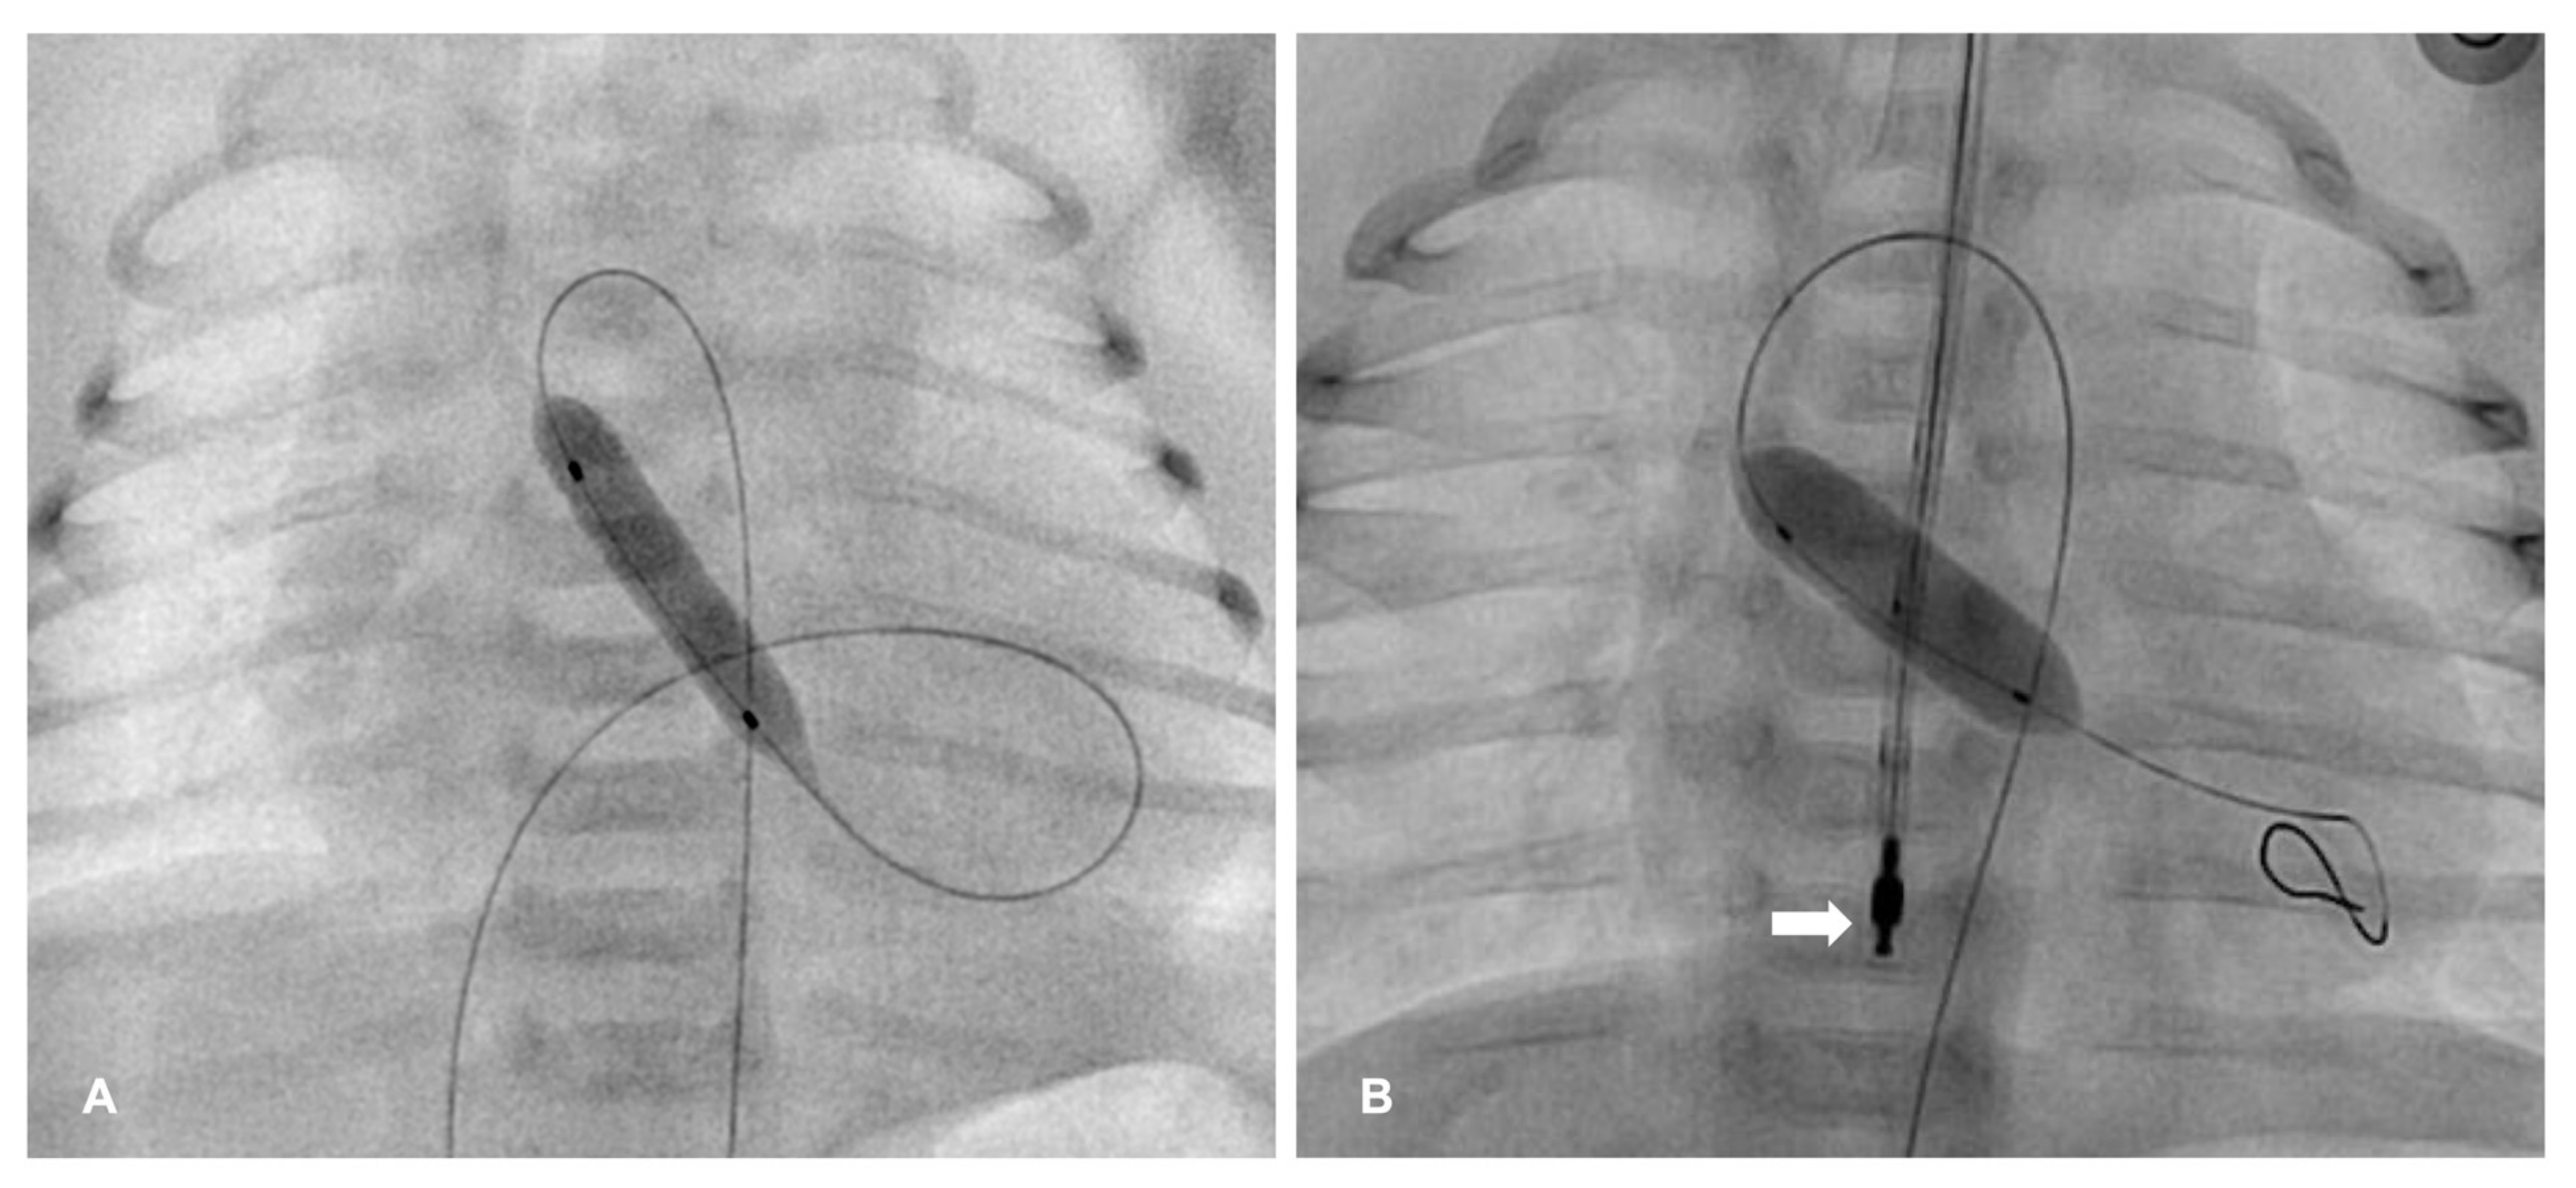

| PDA stenting | Ductus-dependent PBF until next stage of surgery (repair or II stage SV palliation); PA-IVS after PV perforation (inadequate anterograde PBF). | Acute: stent thrombosis, migration and embolization. Late: in-stent stenosis, PA branch jailing. |